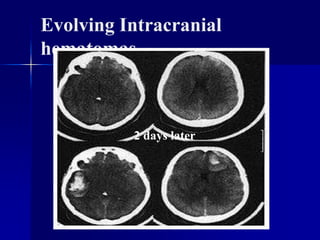

Evolving Intracranial

hematomas

2 days later